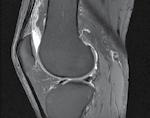

Se practică radiografii standard, examinare CT sau RMN.

CT-ul cu reconstrucție tridimensională sau RMN genunchi relevă mult mai

bine complexitatea fracturii și dau posibilitatea unui planning preoperator superior estimării radiologice clasice(7). CT-ul este mai rapid și mai ușor de făcut, dar RMN decelează mai bine leziunile de menisc sau ligamentare.